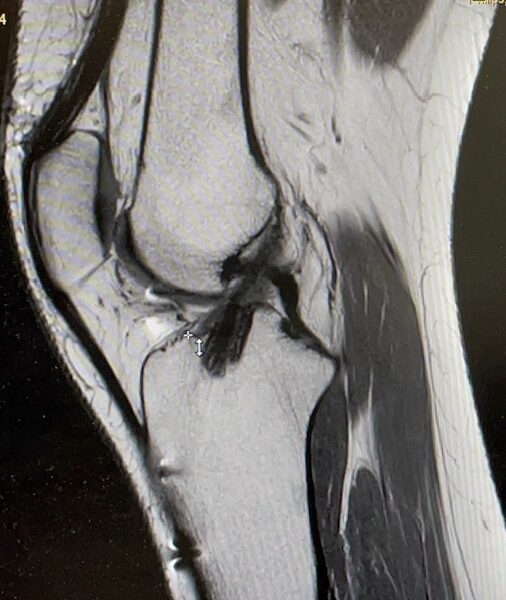

Voorste kruisbandletsel?

De voorste kruisband, één van de belangrijkste band, loopt centraal in de knie. De functie van de VKB is het stabiliseren van de knie in voor-achterwaartse richting. De VKB bestaat uit twee bundels die in feite als één structuur functioneren, is ongeveer 25 tot 40 mm lang en heeft de diameter van een pink. De VKB heeft zenuwuiteinden die de hersenen informeren over de stand en de bewegingen van de knie.

Diagnose

Het letsel van de voorste kruisband wordt bij het eerste onderzoek (bijvoorbeeld op het sportveld, spoed eisende hulp of huisarts) in het merendeel van de gevallen niet onderkend. Het stellen van de juiste diagnose is in de acute fase ook moeilijk omdat er vaak zwelling van de knie bestaat met pijn.

Betreft het in werkelijkheid een voorste kruisbandletsel?